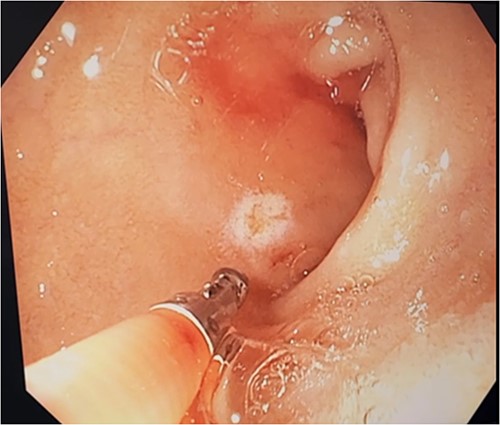

Three days after initial gastroscopy she developed further melena and anaemia, requiring additional PRBCs. She underwent a second gastroscopy, which demonstrated a lesion consistent with a DL at the junction of D1/D2 which was actively bleeding from an exposed vessel (Fig. 3). Haemostasis was achieved with thermocoagulation and adrenaline injection (Fig. 4). The melena resolved and haemoglobin remained stable. The remainder of her admission and 2-month follow-up were unremarkable.

Second gastroscopy – successful haemostasis of actively bleeding duodenal DL with thermocoagulation and adrenaline injection.